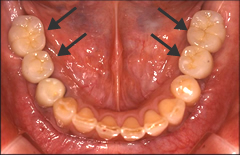

歯を製作するためにお口の中の型を取ります。製作した人工歯をアバットメント(支台部)に装着して完成です。